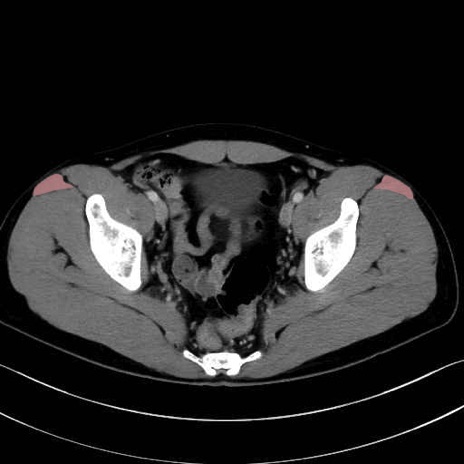

大腿筋膜張筋 (Tensor fasciae latae)